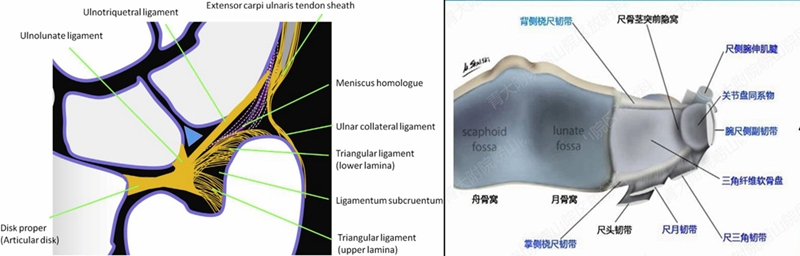

三角纤维软骨复合体(TFCC)是手腕最重要的纤维软骨-韧带复合结构,位于腕关节尺侧,分隔尺腕和远侧尺桡关节。常被称为是腕关节的“半月板”。

TFCC由以下韧带和纤维软骨组成:固有三角纤维软骨(TFC)、背侧桡尺韧带(DRUL)、掌侧尺韧带(PRUL)、尺三角韧带(UTL)、尺月韧带(ULL)、月三角韧带(LTL)、尺侧腕伸肌腱(ECU)鞘、尺侧副韧带(UCL)及半月板类似体(MH)。

半月板同系物是关节盘远侧增厚的尺侧副韧带纤维形成半月板类似体,与关节盘共同起于尺骨背侧靠近尺骨的边缘,有尸解证实其附着于豌豆骨。

半月板同系物